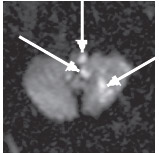

Наиболее часто инфаркт выявляли в области моста (53%) и продолговатого мозга (23%), реже — в области ножек мозга (4%). Нередко инфаркты ствола мозга сочетались с очагами инфаркта в области полушарий мозжечка, затылочных долях мозга (рис. 2).

Рис. 2. Острый ишемический инфаркт ствола мозга и мозжечка (19 ч после развития). ДВИ (аксиальная проекция): в левых отделах родолговатого мозга, левой гемисфере мозжечка определяются гиперинтенсивные очаги, соответствующие острому инфаркту